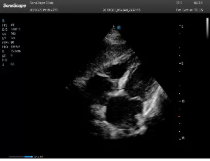

不同的探頭對(duì)應(yīng)于不同的臨床領(lǐng)域,不同的探頭頻率也應(yīng)用于不同的人體組織。超聲波在人體中的衰減與探頭頻率有關(guān),探頭頻率越高,穿透力越弱,分辨率越高,而探頭頻率越低,穿透力越強(qiáng),分辨率越低。因此在檢查淺表器官時(shí)應(yīng)選用高頻探頭,而檢查深部臟器時(shí)則選用穿透性強(qiáng)的低頻探頭。